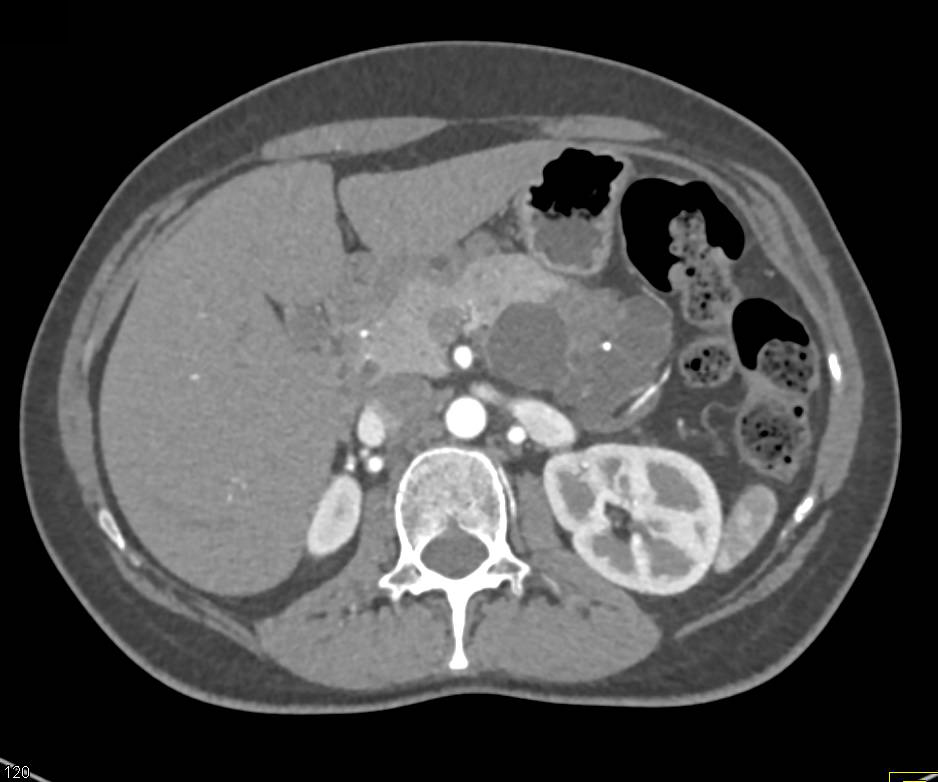

Cystic Neuroendocrine Tumor Head of Pancreas